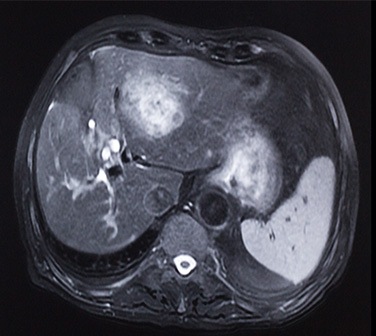

Metástasis hepáticas en cáncer colorrectal

La afectación del hígado por las metástasis de cáncer colorrectal ocasionan una importantemorbilidad (resultando, en ocasiones, en fallo hepático) y son la principal causa de muerte en lospacientes con afectación de este órgano. La resección quirúrgica , el único...